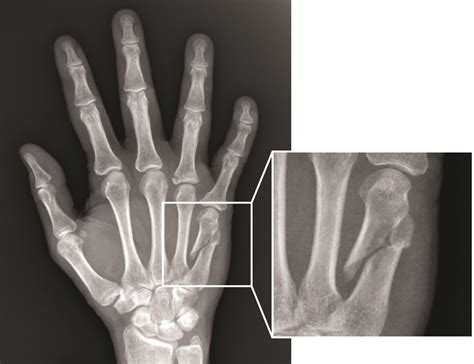

A broken hand, often diagnosed through an X-ray, involves a fracture in one or more of the bones in the hand. The hand is composed of 27 bones, including the metacarpals, phalanges, and carpals. Each of these bones can be susceptible to fractures, which can range from minor cracks to severe breaks.

• X-rays: X-rays are the primary imaging tool used to confirm the presence and type of fracture. They provide detailed images of the bones and can help determine the severity of the injury.

Boxer's Fracture A specific type of metacarpal fracture, often involving the fourth or fifth metacarpal. Punching a hard object with a closed fist.